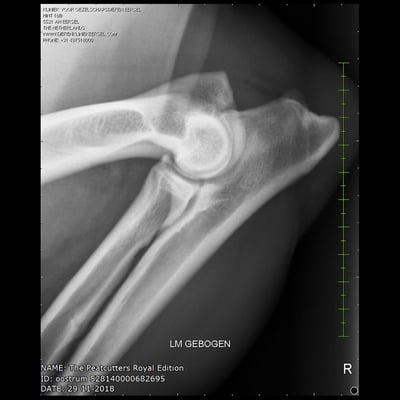

Sjors his official hip and elbow results with the photos. X-rayed at 20 months of age. HD-C, ED-0.